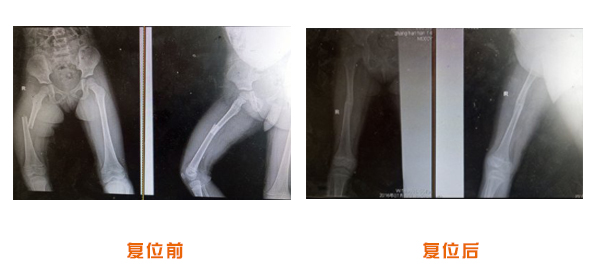

前后對比

復位前后對比